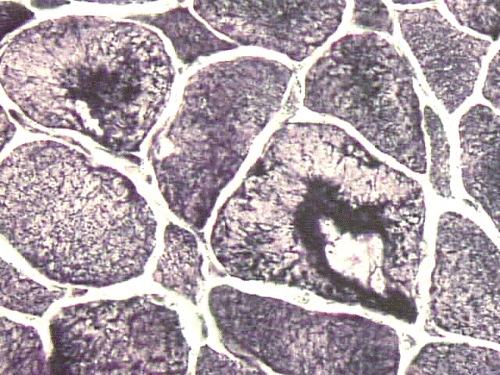

Physical examination revealed weight loss, weakness of arms, and stiffness of joints. He showed no cognitive deficiency and had normal cerebellar function. Muscles in the arm and hands were atrophic.  He had significant weakness of upper extremities and the muscle strength is 2/5 in deltoid, 3/5 in biceps and triceps, and 3/5 in brachioradialis, 3/5 in wrist flexion and extension. He had ulnar palsy in hands for over 10 years with the left side more affected than the right. Significant weakness in the muscle of the hands was also noted. There was no pain in the shoulders on palpation.  Muscle strength in lower extremities was 5/5 in all muscles except for 4/5 in iliopsoas.  The patient could squat up and down without much difficulty.  Sensory functions were intact in proprioception and light touch. There was bilateral decrease in  pinprick below the knees.  Reflexes were trace in upper extremities and were 2/4 knee jerk  and 1/4 ankle jerk.  There were no pathologic reflexes.  The functions of cranial nerve II to XII were intact.  There was good, function in the sternocleidomastoid muscles, but atrophic latissimus dorsi, trapezius, infraspinatus and supraspinatus muscle.  He had percussion tenderness of his bilateral ulnar cubital tunnels and right median tunnel.  Cervical and lumbar spines had full range of movement and were nontender.  CT scan of C-spine showed spondylosis in C3-7.  Head CT showed mild brain atrophy.  Electromyogram and nerve conduction studies of upper extremities were reported as suggestive of motor axonopathy.  Laboratory studies demonstrated slight elebation of rheumatoid factor to16.3, the sedimentation rate was 13, creatine kinase in serum was  171, and Lyme’s test was negative.  A muscle biopsy was perform as part of his workup. Representative photos from the muscle biopsy are shown below:

All stains and histochemistries are performed on frozen materials.

On hematoxylin-eosin stained sections, there is an increased variation of fiber diameter with many atrophic fibers intermingled with fibers of normal caliber. There is no evidence of fiber grouping or perifascicular atrophy. No inflammatory cells are present. There is also mild interstitial fibrosis (Panel A). On higher magnification, many fibers have a round concentric structure (Panel B). Irregular, centrally located depositions are also identified on modified Gomori's trichrome. The concentric nature, however, is not as obvious as in the hematoxin-eosin stained sections (Panel C). Type I and II fibers are not clearly separated in the ATPase preparation at pH 9.4. This is a common situation in chronically ill muscle (Panel D). The type I fibers are unusually dark. There is an increase in the proportion of type I fibers. The atrophic fibers are usually type II fibers. The concentric lesions are found predominantly in type I fibers (Panel E). There is an increase in PAS staining which is consistent with increased glycogen storage (Panel F). No increase in lipid content is demonstrated by oil red O (Panel G). On NADH-TR reaction, the concentric structures appear to have a clear central core that is devoid of enzymatic activity, a rim with intense enzymatic activity and a surround zone with relatively normal reactivity. These features are classic for target fibers (Panel H and I). No deficiency of laminin-2 (merosin) (Panel J) or dystrophin (Panel K) is demonstrated by immunohistochemistry. The central lesions are also immunoreactive for both laminin-2 and dystrophin. Immunohistochemistry for desmin demonstrate a core of strong immunoreactivity and also strong reaction in the sarcoplasmic membrane (Panel L and M). The target structures are also well demonstrated on semithin sections (Panel N). On electron microscopy, z-disc streaming is a common finding and they are often admixed with a substantial amount of dense granular electron dense substance (Panel O and P). There are also numerous cytoplasmic bodies characterized by radiating intermediate filaments (spheroid bodies) (Panel Q and R).